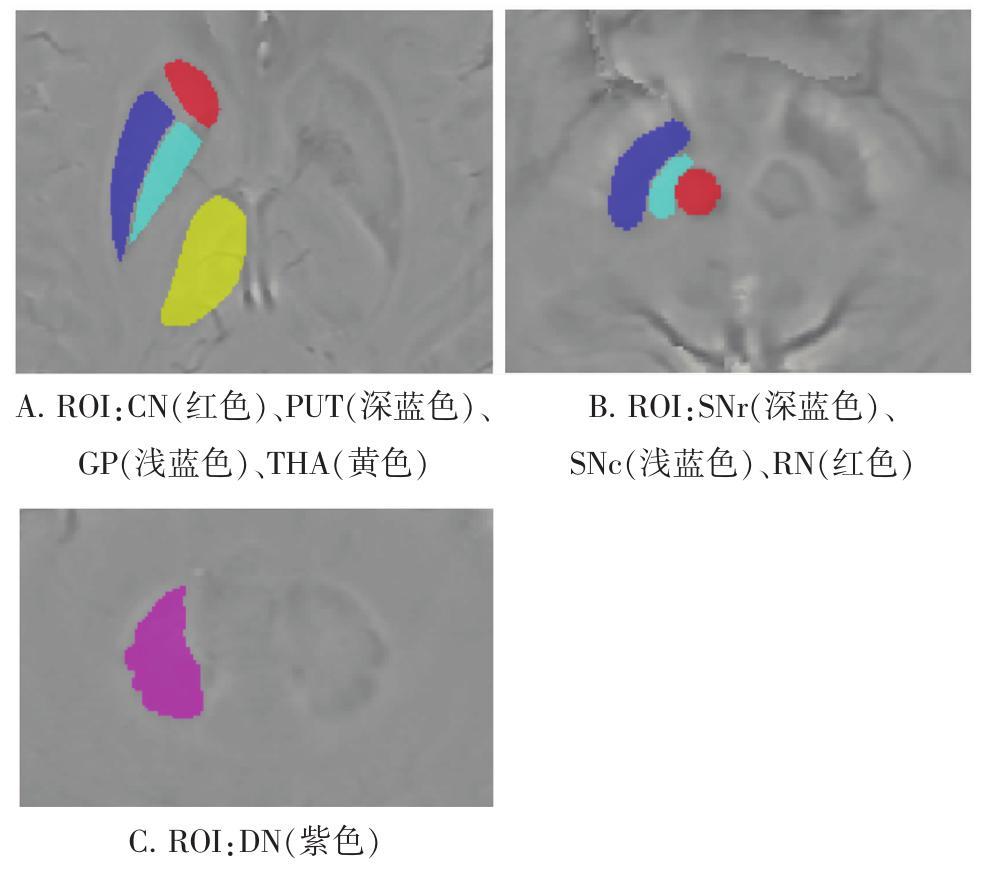

• 应用SWI技术分析帕金森病患者脑铁沉积与运动症状相关性的研究

2021, 46(7):828-833. DOI: 10.13406/j.cnki.cyxb.002860

摘要 (125) HTML (287) PDF 1.39 M (194) 评论 (0) 收藏

摘要:目的: 使用磁敏感加权成像(susceptibility weighted imaging,SWI)检测脑核团铁含量,并评估脑铁沉积与帕金森病(Parkinson's disease,PD)运动症状的相关性。 方法: 纳入35例PD患者和41例年龄和性别匹配的健康受试者在3 T核磁共振完成SWI检查,在相位图中测量各核团的相位值。收集Hoehn-Yahr分级、统一帕金森病评分量表(Unified Parkinson's Disease Rating Scale,UPDRS)第Ⅰ、Ⅱ、Ⅲ部分评分及总分等临床资料。根据Hoehn-Yahr分级将PD组分为早期组(≤2级)及中晚期组(>2级),PD早期组中(Hoehn-Yahr分级≤1.5级)根据其运动症状分为患肢同侧组及对侧组。比较各组间各核团相位值差异,并分析相位值与铁含量、UPDRS评分等的相关性。 结果: 对照组各核团相位值与正常人脑铁含量呈负线性相关(r=-0.809,P=0.028)。PD组黑质致密部(substantia nigra pars compactac,SNc)相位值较对照组显著降低(P=0.011),中晚期PD组SNc相位值显著低于对照组(P=0.014),PD早期患肢同侧组及对侧组SNc相位值差异显著(P<0.001),对侧组SNc相位值较对照组明显降低(P=0.032)。PD组SNc相位值与UPDRS-Ⅱ评分负线性相关(r=-0.364,P=0.032)。 结论: 在PD进展过程中SNc铁含量逐渐增加,以中晚期为著。SNc铁沉积在PD早期的不对称性分布与运动症状不对称有关。PD患者SNc铁沉积与运动症状严重程度呈正线性相关,提示其可能作为监测疾病进展的生物标志物。